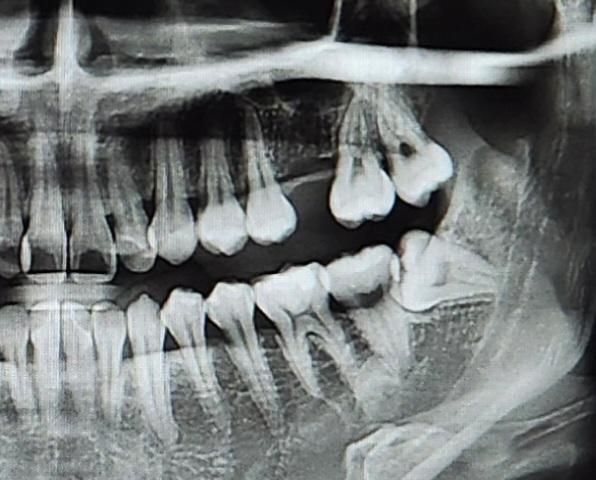

제 1대구치 자리에 임플란트를 하는 경우, 양 옆 치아와 사이 공간이 최소 몇 mm가 있어야 가능할까요?

한 병원에서 뿌리쪽 공간은 괜찮은데 위에 이가 나 있는 부분 공간이 5-6mm정도로 좁아서 교정까지 필요하다는 소견을 들었습니다. 공간이 최소 8mm가 필요하다고 하셨어요. 다른 병원에 가도 다 교정까지 필요할까요? 나이는 20대중반입니다.

흔히 사용되는 4~5mm의 임플란트 두께에 자연치아와의 간격은 최소 1.5mm 이므로 양쪽으로 생각하면 7~8mm의 잇몸뼈 공간이 있어야합니다.

이건 임플란트 뿌리를 위한 잇몸뼈 공간 필요량이고, 병원에서 설명 들으셨다시피 이건 괜찮습니다.

1. 다만, 임플란트 머리부분이 지금 다소 좁은데 이렇게 되면 임플란트 머리(크라운) 가 금방 깨져나갈 수도 있고, 음식물이 잘 낄 수도 있습니다.

2. 교정을 한다면 사랑니 빼고, 두번째 어금니를 조금 뒤로 밀면 될 것 같습니다. 그렇게 복잡한 교정은 아닐 것 같고요

3. 교정을 원치않으시면 두번째 어금니 옆면을 조금 삭제하고 공간을 만들 수도 있습니다.

4. 진단은 당연히 치과마다 다를 수 있습니다. 좁은 공간이지만 심자고 할 수도 있고요. 이건 경험의 차이기도하고, 치료 원칙과 가치관의 차이이기도 합니다.

5. 사랑니랑 그 앞 어금니를 견인해와서 제1대구치 자리로 가져다 두는 교정방식도 있긴 한데 그건 좀 오래걸릴 수도 있고 가능할지는 잇몸, 잇몸뼈 상태 좀 더 체크해봐야합니다.

저정도 공간이면 인접치아의 삭제를 조금 해야 보철물을 올릴공간이 확보될꺼같습니다 추후에 인접치를 다듬으시면될것같습니다.